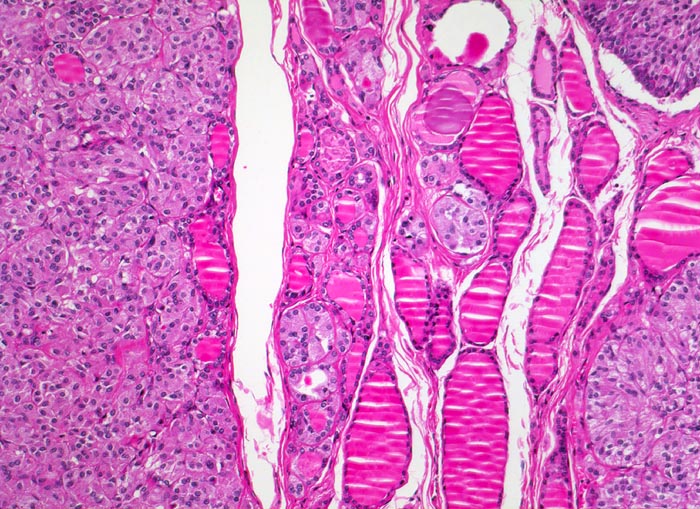

medulläres Schilddrüsenkarzinom bei MEN 2A

Überwiegend solide Tumorknoten aufgebaut aus relativ monomorphen Zellballen, zwischen denen schmale Bindegewebssepten verlaufen. Zwischen den Tumorknoten ist normales Schilddrüsenparenchym mit Herden von hyperplastischen C-Zellen erkennbar.

Mehrere scharf begrenzte weisse Knoten in beiden Schilddrüsenlappen von bis zu 8mm Durchmesser.

Beim Vater der Patientin wurde ein bilaterales Phäochromozytom diagnostiziert und in der Folge eine multiple endokrine Neoplasie vom Typ 2A. Im Familienscreening wurde bei der Patientin eine Mutation im Ret-Protoonkogen nachgewiesen und eine prophylaktische Thyreoidektomie durchgeführt.